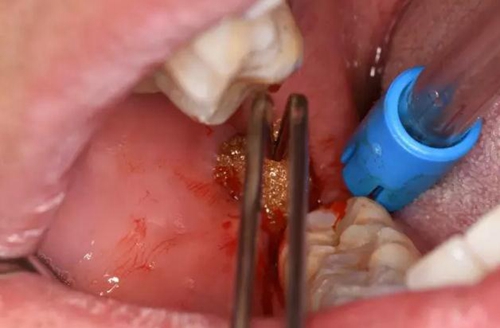

圖9.局部皮膚浸潤麻醉、在膿腫最低部位切開

圖10.充分分離膿腔、使膿液盡量排除

圖11.生理鹽水沖洗

(2)口外局部麻醉不要將麻藥注射進膿腔內(nèi)

(3)切開部位應在膿腫的最低部位,順著皮紋切開

(4)充分分離膿腔,以利于引流通暢,生理鹽水沖洗。